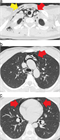

1. 若年でやせ型の男性の胸痛では、特発性縦隔気腫を鑑別診断に挙げることを勧める(推奨度2)

1. 縦隔気腫の誘因となるようなエピソードの後や原因となるような疾患を持つ症例で、胸痛や息切れ・呼吸困難などの症状がみられた場合には、縦隔気腫を鑑別に挙げることを勧める(推奨度2)

1. 胸部X線写真(CXR)で検出しきれない特発性縦隔気腫が少なからずあるため、CXRが正常範囲と判断されても、特発性縦隔気腫が疑われる場合は、積極的に胸部CTを撮影することを勧める(推奨度2)